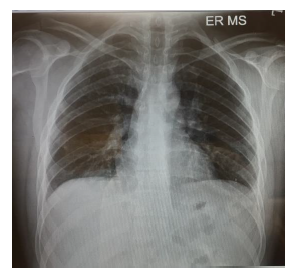

On initial examination in ED (Figure 1), pulse rate (PR) was 110/min, BP- 120/70 mmHg & Peripheral Oxygen Saturation (SPO2) was 89% on room air. An electrocardiogram (ECG) showed sinus tachycardia, and the Chest X-ray was normal. Figure 1 clearly indicates a small wedge-like triangular density in the left lower lobe of the right lung (Humpton’s hump).

Figure 1 ED of the Patient